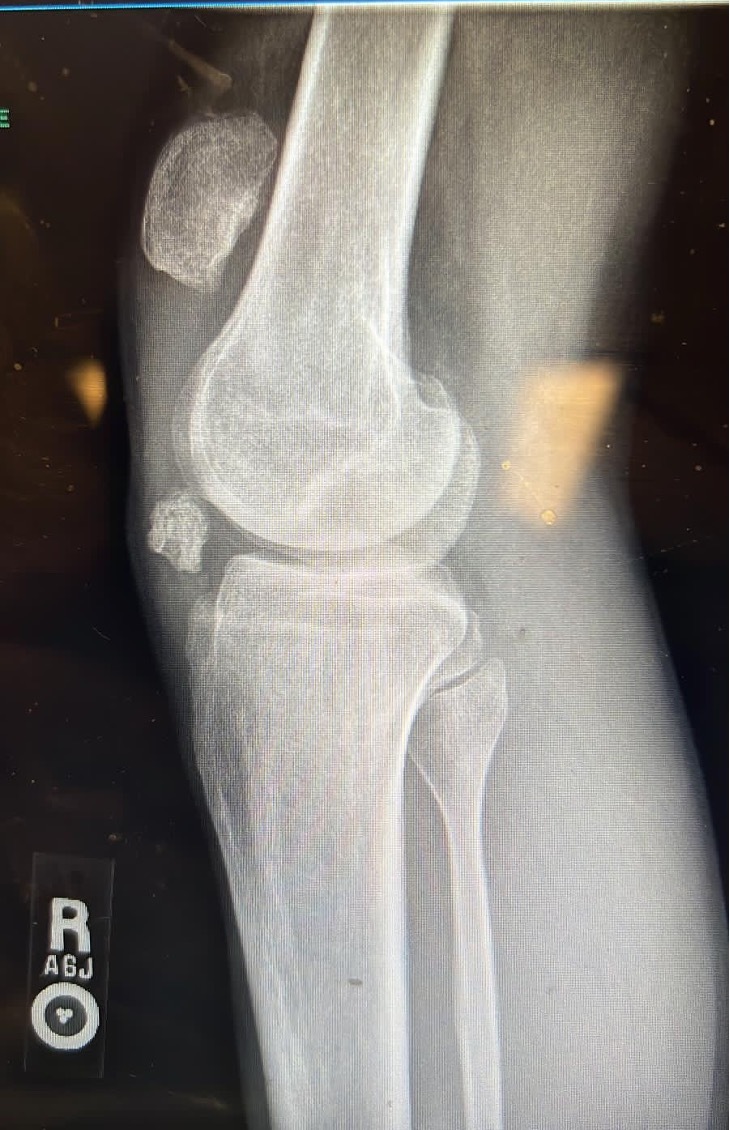

The above findings on physical exam were confirmed using X-ray and MRI scan (Figure 2) which showed a recurrent patellar tendon rupture with patella Alta and a distal pole patella fracture remnant. Risks of the surgery and anesthesia were explained to the patient who agreed with the plan and had all his questions answered.